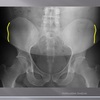

posterior arch of C1

How well did you know this?

1

Not at all

2

3

4

5

Perfectly

10

Q

A

lamina c2-c7